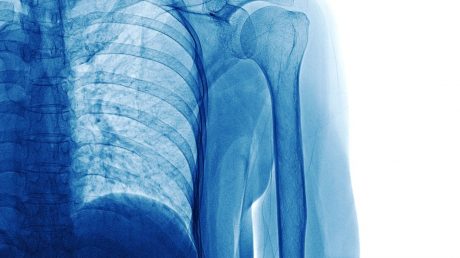

XY was driving in the inside lane of a dual carriageway when a stolen car being driven in the outside lane in excess of the speed limit collided into the offside of her car. This caused XY’s car to leave the carriageway and roll down an embankment. As a result, XY sustained a spinal cord injury and is now an incomplete tetraplegic.

Following the collision, XY was taken to hospital, where she remained in intensive care for several weeks. She subsequently underwent inpatient treatment and rehabilitation and was eventually discharged home nine months later.